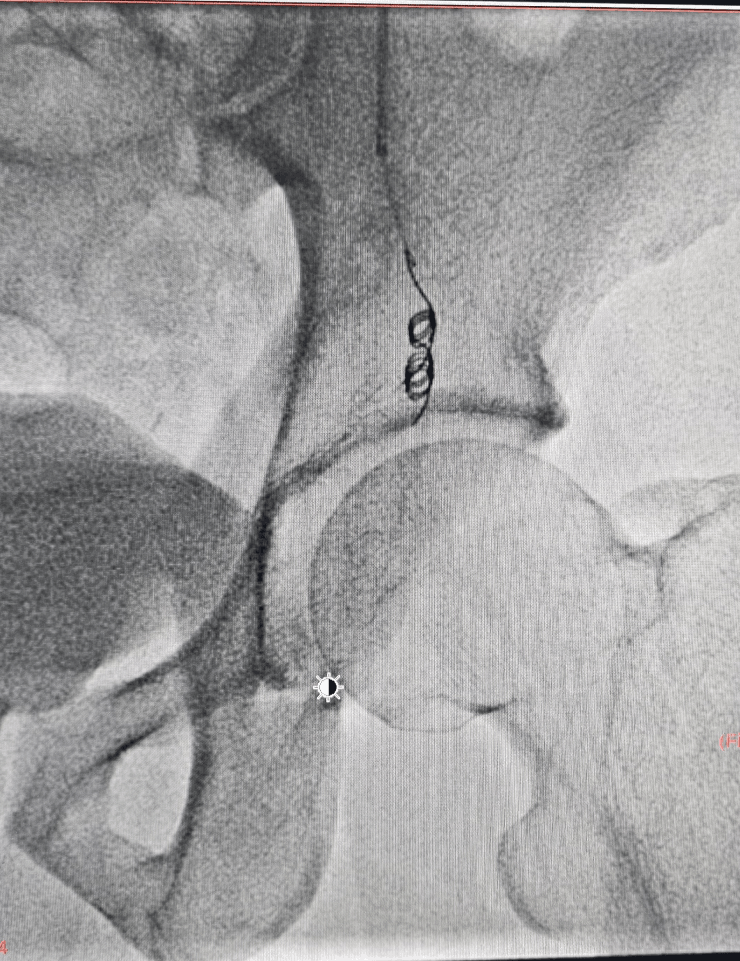

Large left sided varicocele

During embolization, the abnormal testicular veins are blocked from inside using coils and other embolic materials so that high‑pressure blood no longer flows through them. This helps decompress the varicocele and can improve symptoms such as scrotal heaviness, pain and fertility issues.

- Venogram to map abnormal testicular veins and confirm varicocele.

- Coil embolization and/or other embolic agents are used to block the refluxing veins.

- Completion check to ensure there is no further abnormal back‑flow to the scrotal veins.